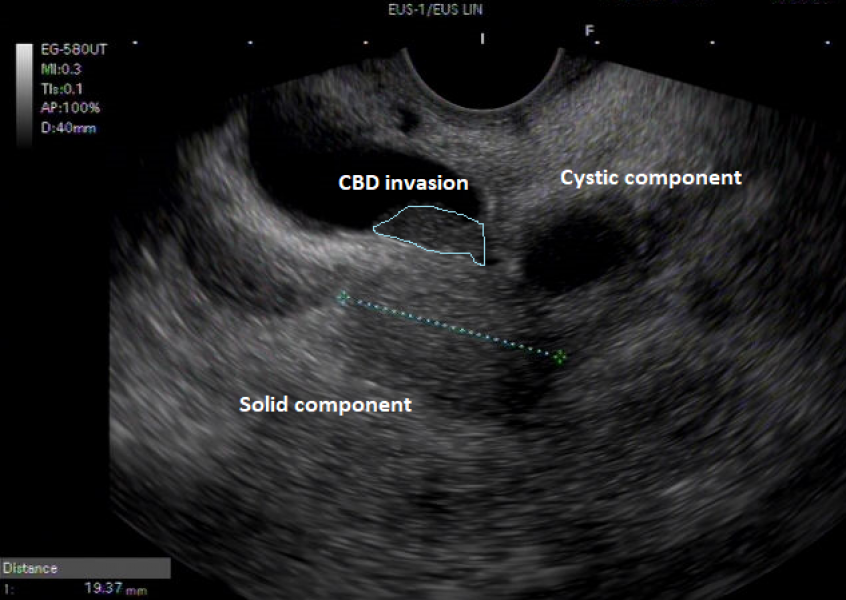

A case of pancreatic tuberculosis